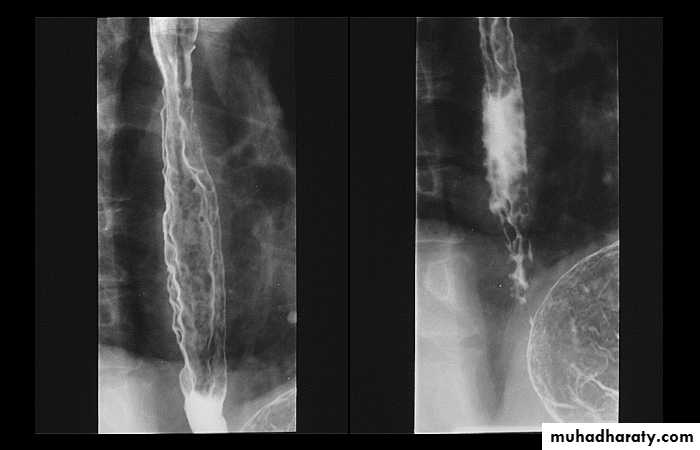

Narrowing :

the narrowing is Constant Short length (confined to cardia).

Regular and smooth.

No shouldering sign.

Tapering (Tip of pencil , cigar shape) Under left dome of diaphragm.

DILATATION (Sac like in proximal part )

Undulating or spiky out line due to sluggish peristalsis.

Non- homogeneity of Barium due to food particles.

Air Barium level.

CXR shows widening of mediastinum.

Absence of fundal gas shadow.

Basal fibrosis in lungs due to repeated aspiration pneumonia .

LEFT: Dilated esophagus (arrows) appears as long, well-defined structure paralleling heart RIGHT: Dilated esophagus usually deviates to right. Narrowing (arrow) at hiatus.